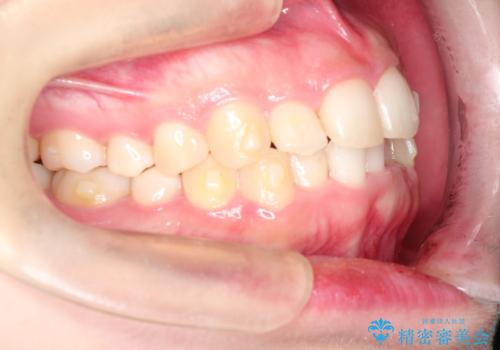

インビザラインでの前歯のガタガタの矯正

- 上下の前歯のがたつきを主訴に来院されました。

歯と歯の間をわずかに削りスペースを作り、インビザラインにて矯正治療を行うこととしました。

使用時間を守っていただけたので、スムーズに矯正を終了することができました。